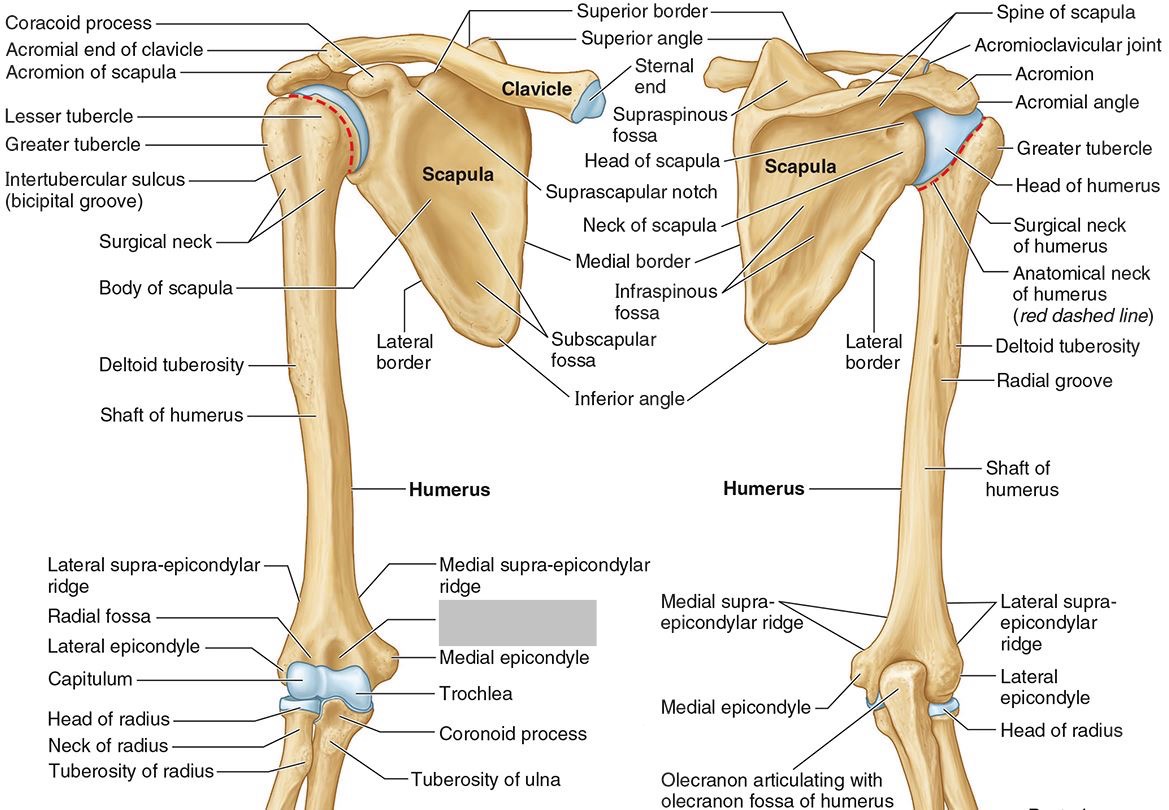

What is the only bone in the upper arm?

The humerus

What part of the humerus is this?

The head of the humerus articulates with the scapula at the glenohumeral joint.

What part of the humerus is this?

The anatomic neck is an indentation distal to the head and provides an attachment for the fibrous joint capsule of the glenohumeral joint.

What part of the humerus is this?

The greater tubercle lies lateral and distal to the anatomic neck.

What part of the humerus is this?

The lesser tubercle lies on the anterior/medial side of the humerus, just distal the anatomic neck.

What part of the humerus is this?

The intertubercular (bicipital) groove lies between the greater and lesser tubercles.

What part of the humerus is this?

The surgical neck is a narrow area distal to the tubercles. It is a common site for proximal humerus fractures.

What part of the humerus is this?

The humeral shaft features the deltoid tuberosity laterally for the distal insertion of the deltoid muscle.

What part of the humerus is this?

The radial groove is an oblique depression that contains the radial nerve and deep brachial artery.

Which parts of the humerus is this?

The medial and lateral epicondyles are distal prominences to which many forearm tendons attach, near the elbow joint.

Which parts of the humerus is this?

The medial and lateral supracondylar ridges extend superiorly from the medial and lateral epicondyles.

Which parts of the humerus is this?

The trochlea and the capitulum (the condyles) are the most distal surfaces of the humerus, where it articulates with the forearm bones at the elbow joint

What part of the humerus is this?

The olecranon fossa is a posterior depression above the trochlea that receives that olecranon process of the ulna

What part of the humerus is this?

The coronoid fossa is an anterior depression above the trochlea that receives that coronoid process of the ulna.